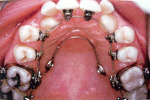

มาถึง การจัดฟันด้านใน

การจัดฟันแบบใสและขั้นตอนการจัดฟันมีรูปคนน่ารักจัดฟันด้วย    การจัดฟันแบบใสและขั้นตอนการจัดฟันมีรูปคนน่ารักจัดฟันด้วย       การจัดฟันแบบใสและขั้นตอนการจัดฟันมีรูปคนน่ารักจัดฟันด้วย

การจัดฟันแบบใสและขั้นตอนการจัดฟันมีรูปคนน่ารักจัดฟันด้วย   >>  การจัดฟันแบบใสและขั้นตอนการจัดฟันมีรูปคนน่ารักจัดฟันด้วย  >> การจัดฟันแบบใสและขั้นตอนการจัดฟันมีรูปคนน่ารักจัดฟันด้วย

>>   การจัดฟันแบบใสและขั้นตอนการจัดฟันมีรูปคนน่ารักจัดฟันด้วย     >>>>>>>  การจัดฟันแบบใสและขั้นตอนการจัดฟันมีรูปคนน่ารักจัดฟันด้วย